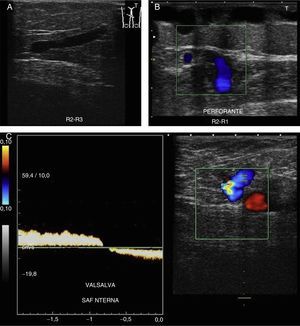

Para demostrar la presencia de reflujo utilizaremos las siguientes maniobras:

Valsalva: aumentando la presión toracoabdominal2,10,11,18 (fig. 8A).

Compresión/relajación distal2,6,10,12: realizar compresión distal hasta que desaparezca el flujo; se considera positivo el reflujo cuando al cesar la compresión se detecta flujo invertido, que se manifiesta como cambio de color e inversión de la curva espectral19,20, en cortes transversales y con Doppler color.

Comenzaremos el estudio a nivel de la unión safenofemoral en modo B (signo de Mickey Mouse) (fig. 8B).

La causa más frecuente de reflujo inmediatamente distal a este punto es la incompetencia de venas tributarias del abdomen inferior o pelvis (vena epigástrica superficial y vena pudenda externa)19,21, especialmente en mujeres multíparas10,19,21 (shunt tipo 4). Las varicosidades vulvoperineales se asocian de forma significativa con el síndrome de congestión pélvica21.